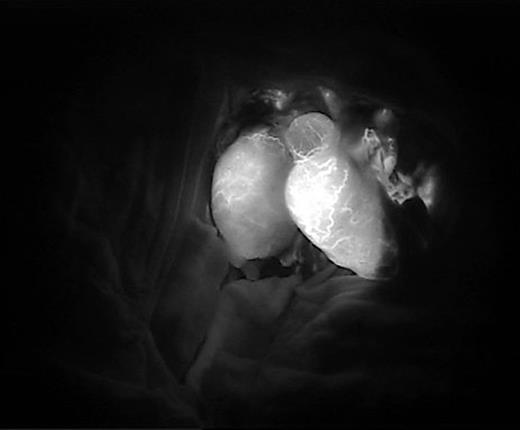

Immediate post-anastomosis indocyanine findings of both testes. Viability of the testes was confirmed.

We performed five examinations to check the viability of the replanted testis. First, in the operating room, we used indocyanine green after replantation (Fig. 4). Indocyanine green fluorescence perfusion showed testicular perfusion, which enabled the immediate checking of the viability of vessels. This procedure is appropriate for checking the viability of microscopic vessels that may be damaged during a milking test. Second, a testicular scan showed the viability of the testis (Fig. 7). One testis is markedly different from the lesion of orchiectomy. However, the scan resolution was low because of a wide range of arterial courses and the disturbance of the urethral catheter or bladder. Third, contrast-enhanced CT displayed the vascularity of the testis and the surrounding parts (Fig. 8). However, the shooting time to the enhanced phase could affect the failure of the vascularity of the testis. No protocol for this case has been established in our institute; therefore, CT was a nonspecific tool for testicular examination. Fourth, ultrasonography efficiently showed the vascularity inside the testis (Fig. 9). However, skin wound could inhibit or limit ultrasonography. Fifth, we indirectly checked the testicular function based on testosterone levels (Fig. 10). A laboratory examination should be performed continuously. However, this procedure could be limited among hypogonadal men, and the separate testicular function of each testis could not be easily identified. Nevertheless, these techniques will help determine the viability of the testis in specific situations.